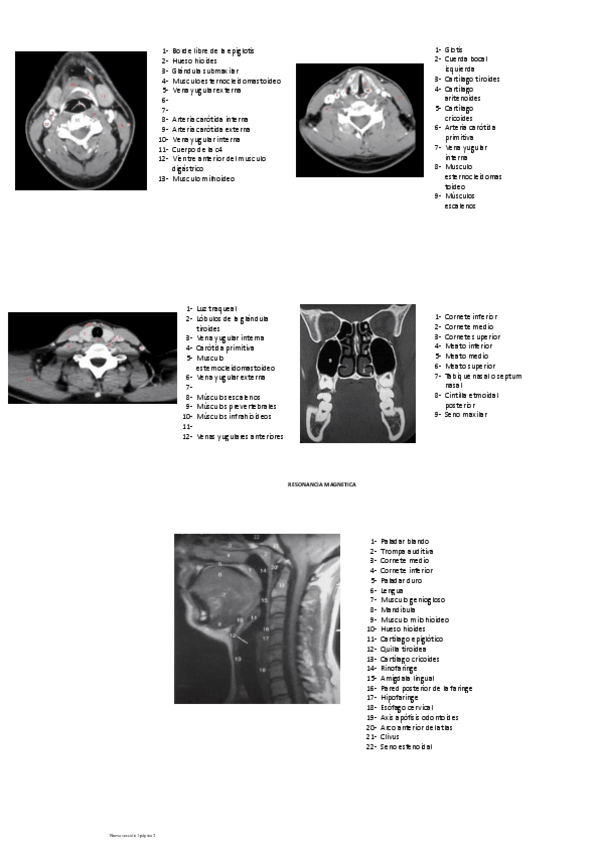

He publicado nuevos apuntes de 1º Medicina Familiar I: IMAGENOLOGIA-DE-CARA-Y-CUELLOO.pdf

3 páginas